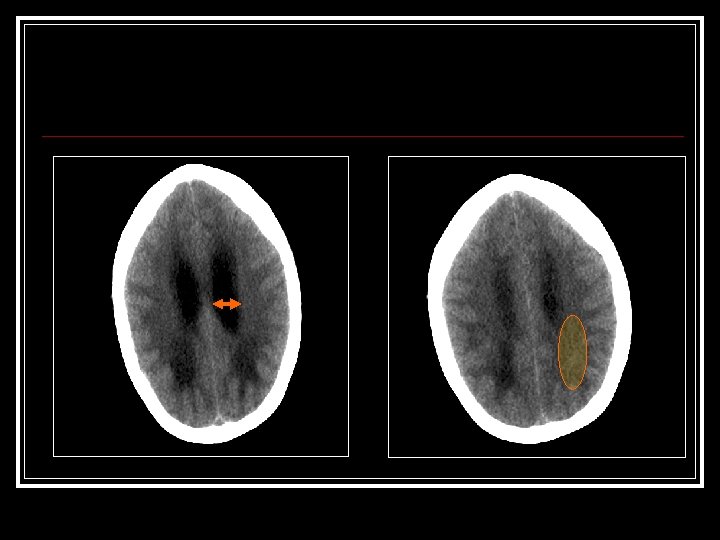

CCU: n Gets Repeat CT

March 22 [cont’d] n n n Neuro. Surgery Consulted ? Shunt Malfxn Initial exam: Intub, withdrawing disconjugate gaze Drain off 20 cc via shunt reservoir Pt immediately awakes, begins reaching for ETT Cannot palpate distal shunt got AXR: